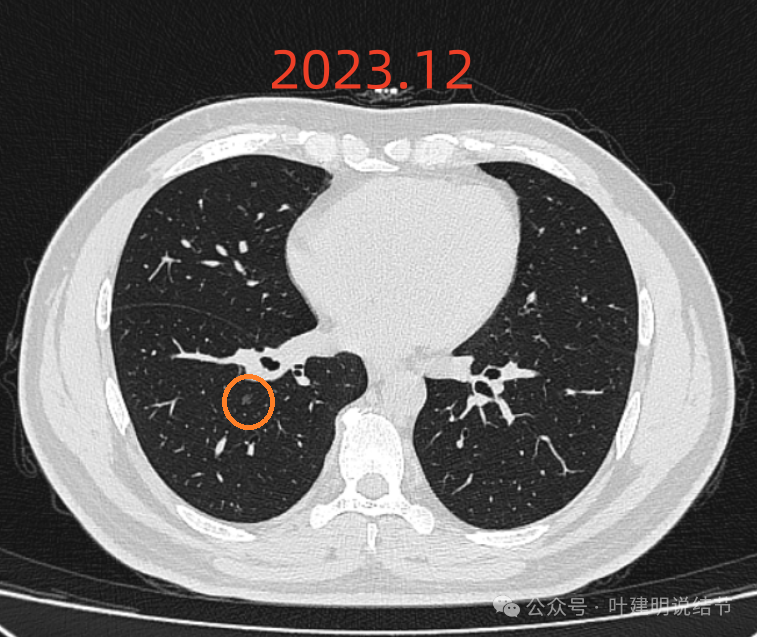

2023年12月时的右下病灶与2022年5月时无明显变化,似乎稍显明显点。边缘欠平滑,有细毛刺样,但密度仍是低的。

2024年7月时右下病灶感觉比2023年12月的反而略有好转,当然这应该是扫描层面的关系,但至少说明与2022年5月比并无明显进展的。